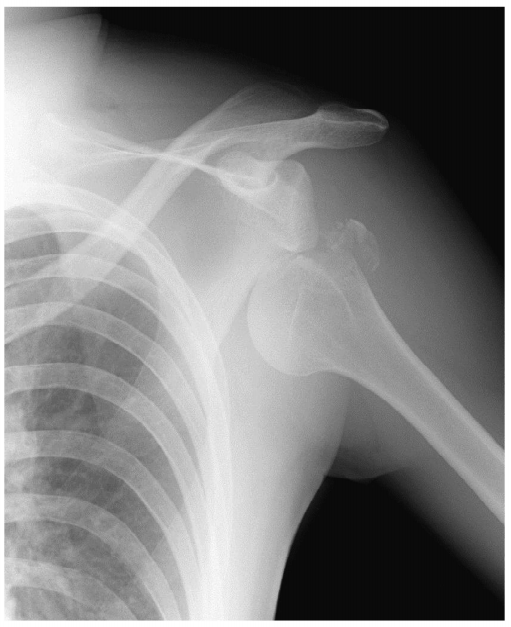

30歳の男性。スキーで転倒して受傷した。エックス線写真を別に示す。肩脱臼整復後に肩関節内転・内旋位で固定されたが、上腕の外側上部に感覚鈍麻を訴えた。

合併症の神経麻痺はどれか。